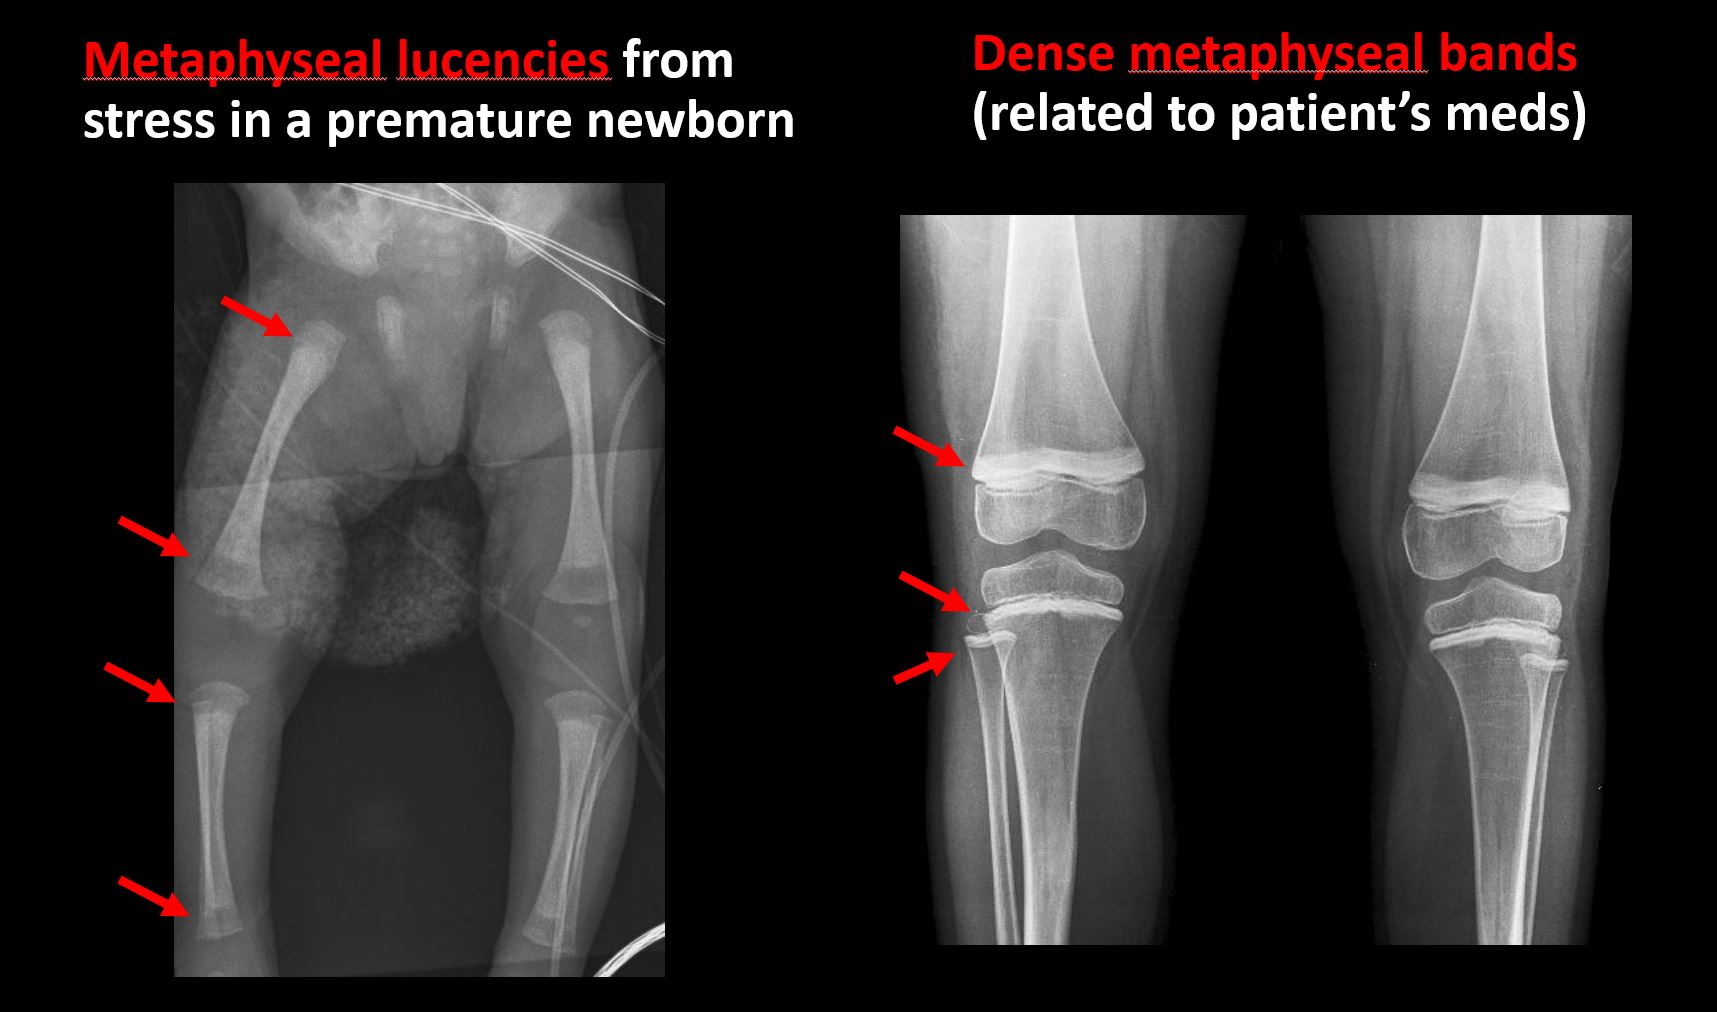

There is metaphyseal abnormality (lucencies, increased density, erosion) which may be from something other than injury such as stress, metabolic disease (e.g. rickets), neoplasm (e.g. leukemia), heavy metals, inflammation, or infection. |

No | NA |